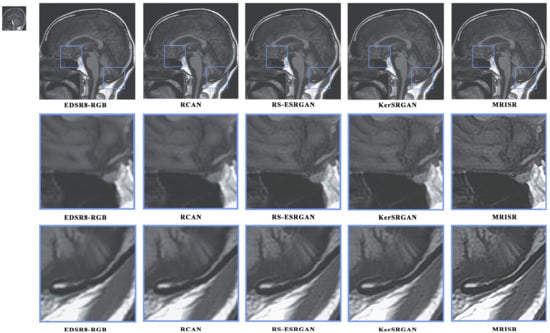

Figure 16 and Figure 17 present a visual comparison of images generated by different algorithms, with the objective of conducting a comprehensive analysis of the performance of various models in the task of image super-resolution reconstruction. Through a detailed examination of images featuring complex terrains, it is evident that, due to the inherent limitations of traditional interpolation algorithms, such as the bicubic method, the processed images exhibit a high degree of blurring and smoothing, ultimately resulting in a significant loss of detailed information. In contrast, while advanced deep learning models, like EDSR8-RGB, RCAN, and RS-ESRGAN, have demonstrated notable advancements in image super-resolution reconstruction, they still exhibit certain deficiencies in accurately distinguishing noise with sharp edges, leading to blurred outputs and unsatisfactory detail recovery. The proposed MRISR model in this paper, however, introduces innovative noise estimation and reconstruction strategies, resulting in generated images that exhibit clearer boundaries between objects and backgrounds, along with more accurate detail recovery. This indicates that our estimated noise distribution is closer to the real noise, thereby effectively enhancing the overall quality of image super-resolution reconstruction. When compared with models such as EDSR8-RGB, RCAN, and RS-ESRGAN, the results of the proposed MRISR model exhibit significantly improved visual clarity, richer details, and no blurring artifacts, fully demonstrating its superiority and effectiveness in the task of image super-resolution reconstruction.

Figure 16. Visual comparison of the generated images.